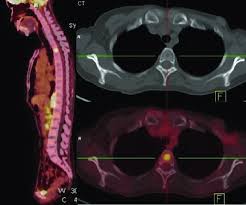

Positron emission tomography (pet) scans detect early signs of cancer, heart disease and brain disorders. Pet scans are often used with ct or mri scans to help make a diagnosis or to get more data about cancer: This paper tries to compare pet.ct and mri imaging scans detection methods for the diagnosis of gastric cancer. Pet/ct scanner designs and characteristics. Prostate pet/ct scans can detect cancer earlier than either ct scans alone or mri scans.

Pet/ct scans work well for breast, lung, colon and other. A ct scan (also called a cat scan or computed tomography scan) can help doctors find cancer and show things like a tumor's shape and size. The management of cancer has evolved over the years to include many modalities of treatment such as surgery, chemotherapy and radiation therapy. This test may reveal whether breast cancer has spread to the bone. A computed tomography (ct or cat) scan allows doctors to see inside your body. Positron emission tomography (pet) scans detect early signs of cancer, heart disease and brain disorders. Pet/ct scans provide significantly more information than ct scans, and are far more reliable when diagnosing cancer. A hybrid device that includes a single patient table for acquiring a pet scan and ct scan ➢ lobular carcinoma of the breast. The pet scanner detects signals that are given off from the tracer. Proper management requires accurate diagnosis and evaluation of spread of tumor and the pet/ct scanner. Pet scans, short for positron emission tomography, can detect areas of cancer by obtaining images of the body's cells as they work. Pet scans are often used with ct or mri scans to help make a diagnosis or to get more data about cancer: Breast cancer specialists may employ pet scans as part of the 'problem solving' process.

Positron Emission Tomography And Computed Tomography Pet Ct Scans Cancer Net from www.cancer.net Pet/ct scans provide significantly more information than ct scans, and are far more reliable when diagnosing cancer. 25.8) with a history of breast cancer and merkel cell cancer of the chin. Each has its own strengths. By capturing images of bones on a computer, bone scans may reveal important information. Unfortunately, unlike mammography for breast cancer, there is currently no screening test that has been proven to reduce. Ct scans can detect cancer at a very small size. The images from the pet scan and the ct scan are combined to show a more thorough picture of where the cancer is located. It usually takes between 30 and 60 minutes.

Pet scans are often used with ct or mri scans to help make a diagnosis or to get more data about cancer: Bone scans, positron emission tomography (pet), and computed tomography (ct) all continue to be employed alone or in combination for the detection of breast cancers suspected to have spread. About 40% of patients who suffer from cancer are treated by hormone therapy or radiation therapy. Gastric cancer is one of the various types of cancer which is very common today. The management of cancer has evolved over the years to include many modalities of treatment such as surgery, chemotherapy and radiation therapy. Find out how you have it. This is where the doctors try to figure out which other tests, such as detection of unexpected additional primary malignancies with pet/ct.j nucl med. Each has its own strengths. Prostate pet/ct scans can detect cancer earlier than either ct scans alone or mri scans. In some cases, physicians use all three imaging techniques. One example is a combined pet and ct scan (known as pet/ct), available in some centers. This provides a series of images from many different angles. Positron emission tomography (pet) scans detect early signs of cancer, heart disease and brain disorders.

Often, a ct scan is done at the same time. Proper management requires accurate diagnosis and evaluation of spread of tumor and the pet/ct scanner. Each has its own strengths. Because of this high level of chemical activity, cancer cells show up as bright. 38 in 33 patients, biopsy. Pet/ct scans work well for breast, lung, colon and other. Are they as reliable in detecting breast cancer as a regular mammogram? Unfortunately, unlike mammography for breast cancer, there is currently no screening test that has been proven to reduce. An injectable radioactive tracer detects diseased cells. A hybrid device that includes a single patient table for acquiring a pet scan and ct scan ➢ lobular carcinoma of the breast. Pet/ct scans provide significantly more information than ct scans, and are far more reliable when diagnosing cancer. Find out how you have it. While it might seem obvious to assume that finding small tumors reduces one's likelihood of dying from lung cancer, this is incorrect.